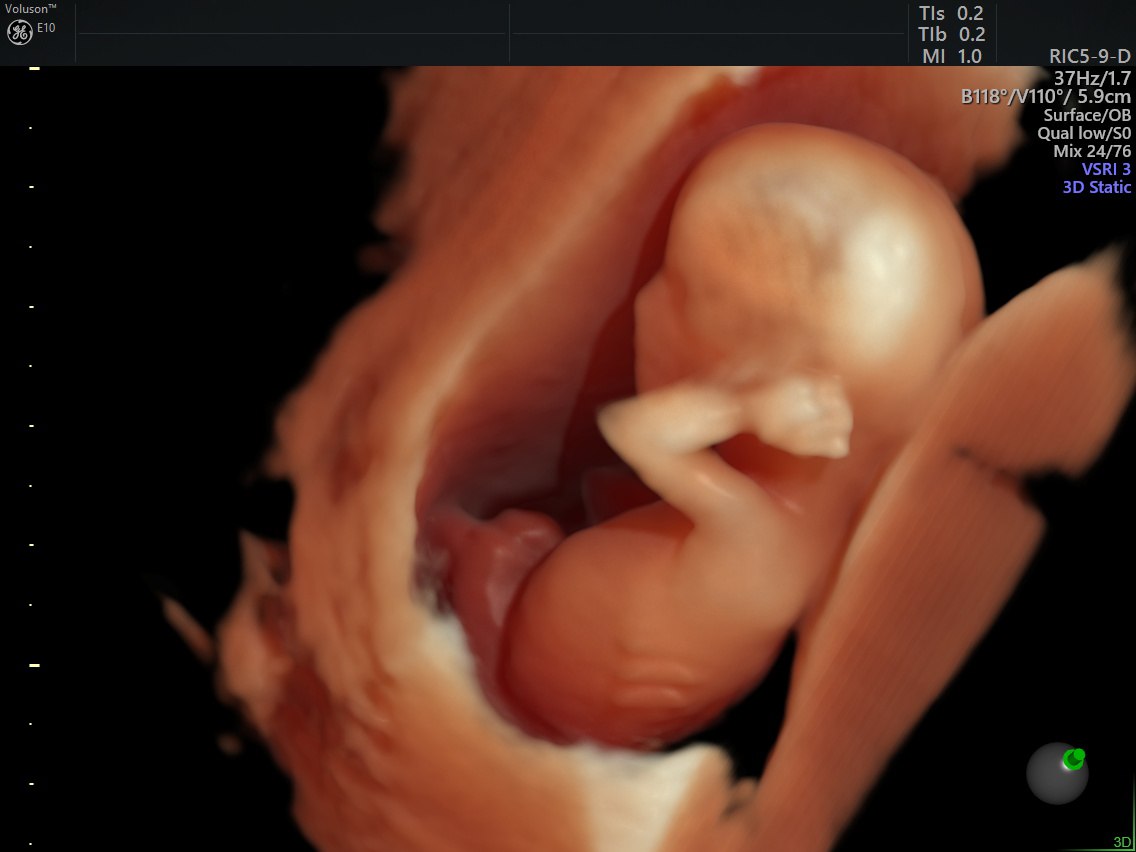

Сегодня медицина дает женщинам всё больше возможностей для реализации материнства, даже в возрасте, который еще недавно считался репродуктивно неблагоприятным. ЭКО после 50 лет — не редкость. Однако за этим стоит целый комплекс медицинских нюансов, о которых важно знать заранее.

Женщина может вступить в программу ЭКО и после 50 лет, особенно если менструальный цикл ещё сохраняется. Однако даже при этом шансы на успех с использованием собственных яйцеклеток равны нулю. В таких случаях единственным методом считается ЭКО с донорскими яйцеклетками. Это означает, что для зачатия используются клетки молодой здоровой женщины донора. Оплодотворение происходит методом ЭКО в лабораторных условиях, и далее эмбрион переносится в матку женщины-пациентки.